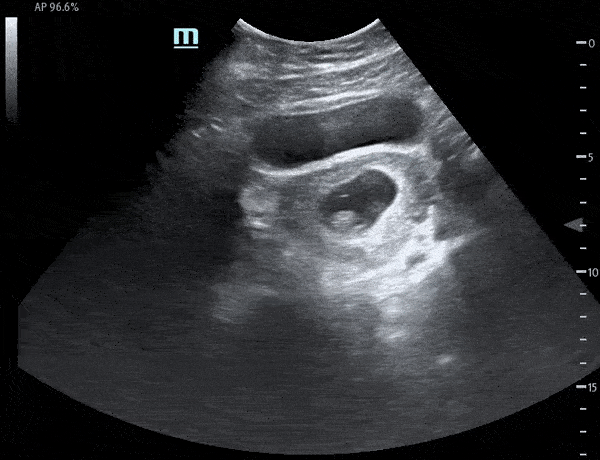

Transverse view of uterus demonstrating fetal pole. A subtle flicker within the fetal pole can be seen consistent with cardiac motion. Michael Macias